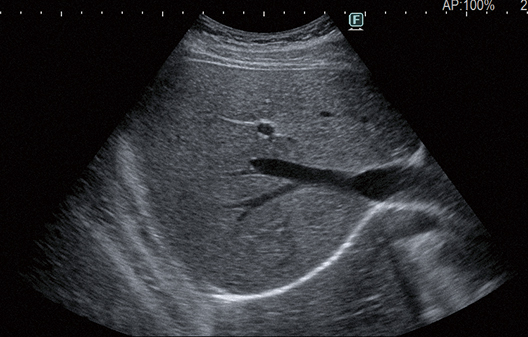

Tecnología de imagen avanzada que produce imágenes con “visibilidad más clara”*. Las imágenes estables con menos dependencia del paciente ayudan a lograr imágenes más claras con menos ruido. Esto es posible gracias a nuestra nueva tecnología de procesamiento de imágenes que mejora la visibilidad de la estructura del tejido.

Como concepto de esta función, nos gustaría poner énfasis en la “visibilidad más clara”.

- * “Visibilidad más clara” debido a la reducción del ruido, la integridad mejorada y la continuidad de los límites de los tejidos.

APAGADO

ENCENDIDO